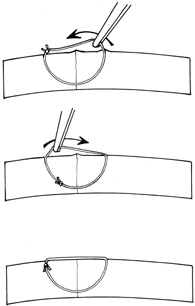

A number of options are available for suturing a corneal laceration. Tissue margins should appose as precisely as possible while suturing. The simplest method is to progressively halve the wound with simple interrupted sutures. Corneal sutures should be approximately 90% to 95% depth through the stroma, 1.5 mm in length, and of equal depth on each side of the wound. Shallow sutures create internal wound gape, whereas sutures of unequal length and depth on each side of the wound result in wound override. Sutures should generally not be passed through 100% thickness because the tract may theoretically act as a conduit allowing microorganisms from the external surface to enter the eye. For shelved lacerations, sutures should be placed equidistant with respect to the internal aspect of the wound and tied with minimal tension to achieve good tissue apposition, avoiding wound slippage with consequent tissue override (Fig. 5). Wounds with edematous or irregular margins generally require longer sutures for closure.